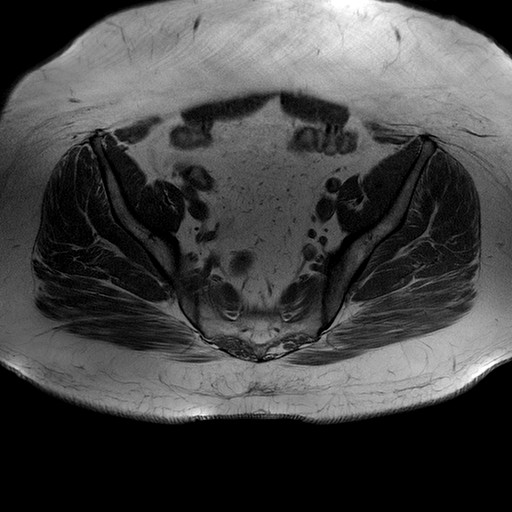

Esami: RMN BACINO

T1W_TSE

Evidenti e simmetriche alterazioni osteofitosiche in regione coxo femorale con riduzione delle rime articolari. Degenerazione completa del cercine glenoideo. Non attuali segni di versamento articolare. Non segni di edema osseo che escludono attuale algodistrofia od osteonecrosi. Lieve e simmetrica riduzione del trofismo della muscolatura glutea.